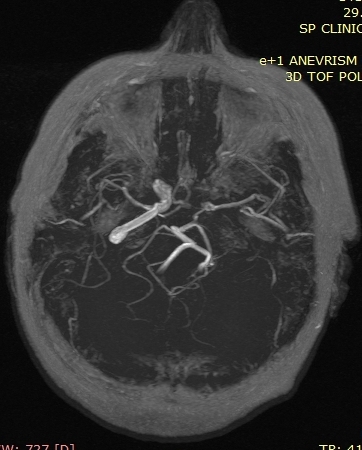

A new case of a 50-year-old female who presented with left otorrhagia caused by an internal carotid aneurysm is reported. No medical history of tinnitus, vertigo, otalgia or otorrhea. Middle ear surgery was effective in resolving bleeding and did not cause any permanent neurological deficit. High resolution computed tomography angiography is the technique of choice and, in some cases, can be complemented with a magnetic resonance angiography. Misdiagnosis of the internal carotid artery aneurysm may lead to serious morbidity because of bleeding or vascular occlusion.